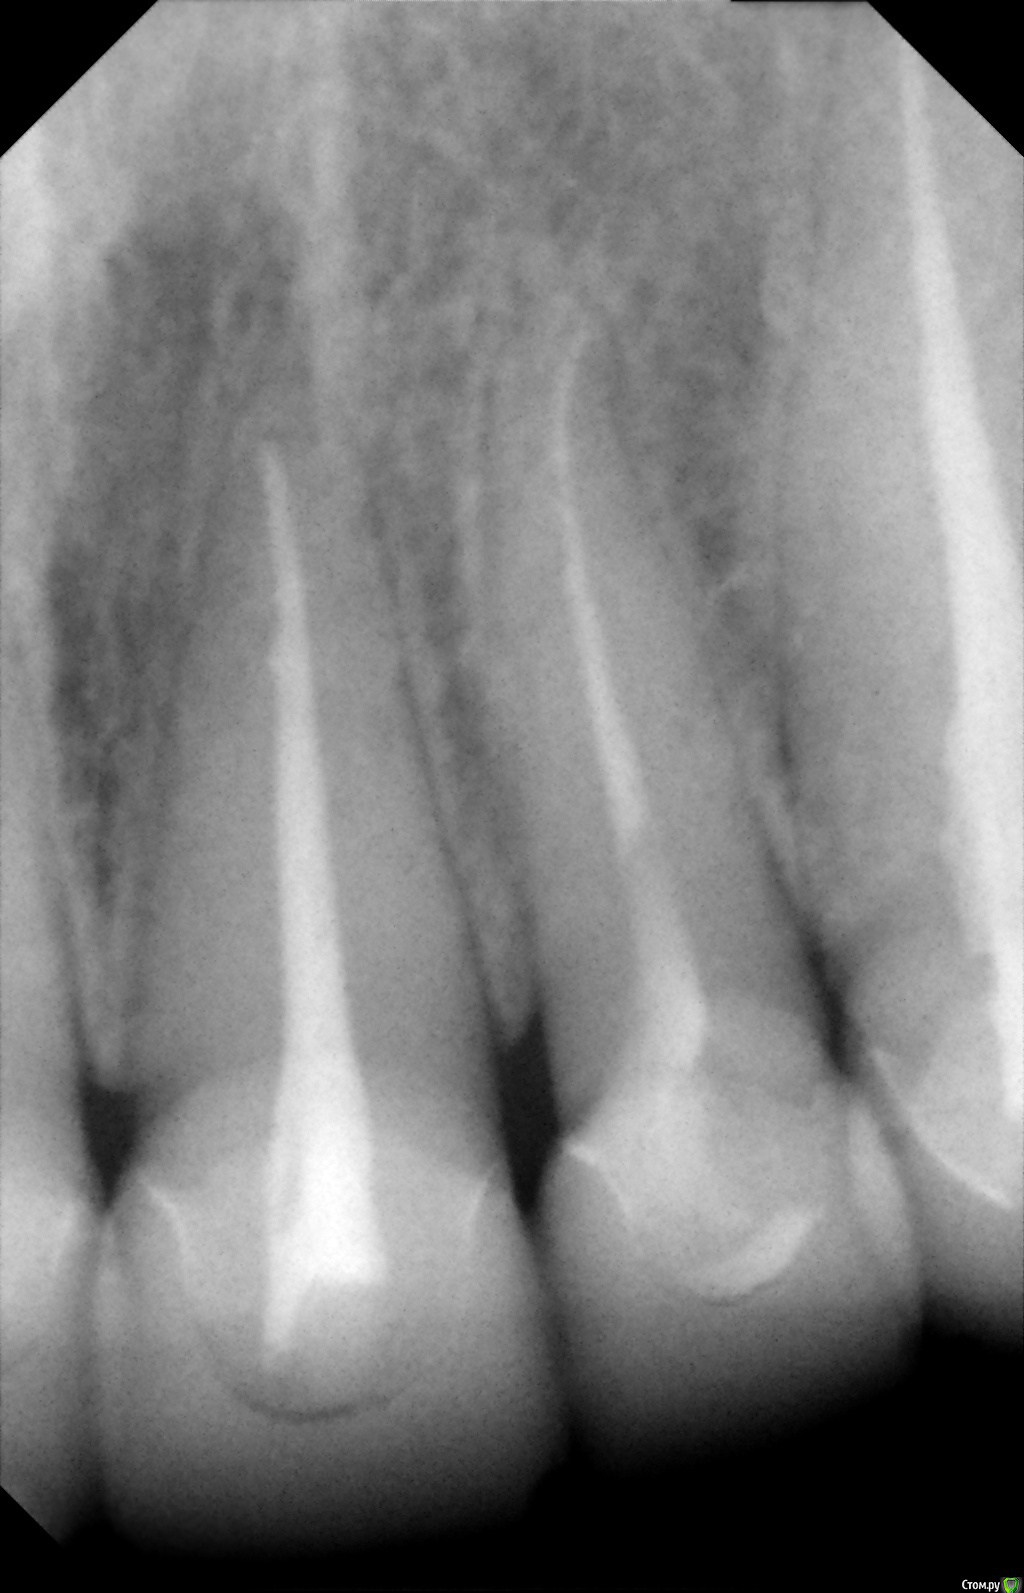

Alexandr_doc Опубликовано 21 сентября, 2018 Поделиться Опубликовано 21 сентября, 2018 Доброго всем времени! Пациентку протезировал доктор, которого уволили по ряду причин, обратилась ко мне на этапе после протезирования с жалобами на болезненность в области фронтальной группы зубов 1.2, 1.1, 2.1, 2.2, 2.3 при дотрагивании языком или пальцем. Перкуссия положительная как в вертикальном так и горизонтальном направлении. Установлены одиночные керамические коронки на каркасе из диоксида циркона. Отек, покраснение в области переходной складки отсутствует, также отсутствует болезненность при пальпации. Подвижность 1 степени. Прилагаю фотографии на этапе обращения. Ранее, на этапе протезирования было принято решение о депульпировании фронтальной группы тк присутствовала пульпитная симптоматика, после чего состояние улучшилось и остается стабильным по сей день. Предположил несколько причин оставшейся симптоматики: 1) несостоятельно проведенное эндо лечение - вариант отмел тк по прицельным снимкам и кт отсутсвуют очаги воспалительных процессов 2) некорректно изготовленные искуственные коронки ( глубокая поддесневая препаровка и агрессивный контур коронки ) 3) - окклюзионная перегрузка. Совместно с пацинеткой принято решение о снятии коронок во фронтальном отделе, была предупреждена о том, что возможно не получить хорошей динамики. С переменным успехом картина после нескольких корректировок временных коронок остается преждней. Болезненность на прежднем уровне, плюс по ходу наблюдения пришлось снять мост с опорой на уровне имплантатов, тк имели место быть воспалительные процессы в проекции имплантата 1.5. С удовольствием отвечу на все вопросы и приму любую критику. Ссылка на комментарий

Alexandr_doc Опубликовано 21 сентября, 2018 Автор Поделиться Опубликовано 21 сентября, 2018 Маргинальной гингивит. Нависающие края? Мягкий налет под коронками? Остатки цемента? Скоро будет пародонтит.Специально приложил прицельные снимки с временными коронками, где нависающие края? Цемента, лежащего тоннами там нет, думаю, что с корявыми временными коронками выкладывать пост не стал бы Ссылка на комментарий

Alexandr_doc Опубликовано 21 сентября, 2018 Автор Поделиться Опубликовано 21 сентября, 2018 Точно ли на кт нет изменений на корнях зубов? Мне на рентгеновских снимках что-то видится. жесткая каппа на верхний зубной ряд - я бы начал с этого.Нижние резцы устойчивы?Чем вам не нравится глубокая поддесневая препаровка? Десна выглядит также как и на интактных зубах НЧ.Как проверяется работа на предмет локальной перегрузки - не знаю, расскажите пожалуйста.На кт изменений нет, мне хотелось их найти, но нет. Мне будет не сложно сделать срезы и приложить их к посту, рассматривал некачественное эндо как один из первых причинных факторов. Жесткая капа какая? Какой дизайн и схему порекомендуете? Десна действительно сейчас выглядит также как и в других участках. При гипсовке в ЦС проверены: наличие первого контакта на фронтальной группе, проверена схема направляющих, распределение контактов на моделях. Ссылка на комментарий